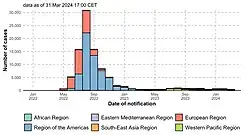

In May 2022, the World Health Organization (WHO) made an emergency announcement of the existence of a multi-country outbreak of mpox, a viral disease then commonly known as "monkeypox".[7] The initial cluster of cases was found in the United Kingdom,[8] where the first case was detected in London on 6 May 2022[9] in a patient with a recent travel history from Nigeria where the disease has been endemic.[10] On 16 May, the UK Health Security Agency (UKHSA) confirmed four new cases with no link to travel to a country where mpox is endemic.[9] Subsequently, cases have been reported from many countries and regions.[11] The outbreak marked the first time mpox had spread widely outside Central and West Africa. The disease had been circulating and evolving in human hosts over several years before the outbreak and was caused by the clade IIb variant of the virus.[12]

On 23 July 2022, the Director-General of the WHO, Tedros Adhanom Ghebreyesus, declared the outbreak a public health emergency of international concern (PHEIC), stating that "we have an outbreak that has spread around the world rapidly, through new modes of transmission, about which we understand too little".[13] A global response to the outbreak included public awareness campaigns in order to reduce spread of the disease, and repurposing of smallpox vaccines.[14][15]

In May 2023, the World Health Organization declared an end to the PHEIC, citing steady progress in controlling the spread of the disease.[16] Relatively low levels of cases continued to occur, and as of 30 June 2025, there have been a total of 150,889 confirmed cases and 377 deaths in 137 countries.[17][18][19]

Further cases in multiple countries outside the endemic area were reported through the second half of May 2022. On 18 May, Portugal reported 14 cases of mpox.[76] In Spain, there were seven confirmed cases as of 18 May.[77] On the same day, the United States confirmed its first 2022 case of mpox and Canada reported 13 suspected cases.[78][79]

On 19 May, Sweden, Belgium[80][81] and Italy confirmed their first cases.[82] On 20 May, Australia,[83][84] Germany, France and the Netherlands confirmed their first cases.[85][86][87] For the remainder of May, multiple European countries[88][89][90][91] and Israel confirmed their first cases.[92][93] The United Arab Emirates[94] and Mexico also confirmed their first cases.[95]